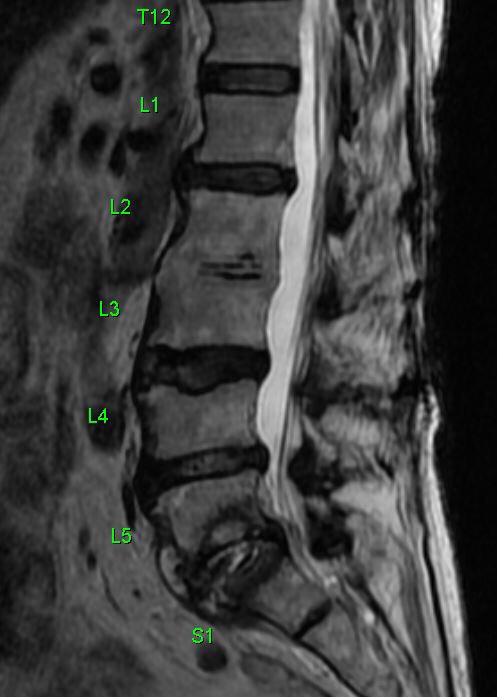

An X-ray of the lumbosacral spine showed narrowing of the L2-L3 disc space following which an MRI of the spine was arranged. Blood cultures were positive for Streptococcus bovis.

The MRI showed degenerative changes at L2-L3, but more importantly, spondylodiscitis at S1-S2, with impingement of nerve roots (which would explain the symptom of buttock pain. This is most plausibly attributed to the Streptococcus bovis bacteremia.